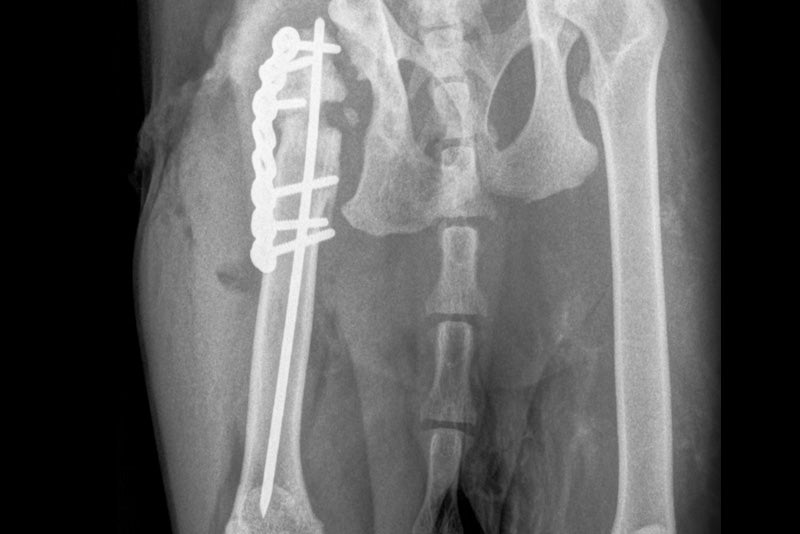

Beim zweiten Fall handelte es sich um eine 8 Jahre alte Katze mit einer Non-Union einer Femurfraktur, welche vor Jahren offenbar mit 4 Kirschnerdrähten und einem Fixateur externe behandelt wurde. Die Katze litt nun an Hüftschmerzen. Bei der  Revisionschirurgie wurde eine Femurkopfresektion durchgeführt, die Implantate wurden entfernt und instabile Stelle am Femur mittels Ostektomie der Fragmentenden vorbereitet. Dann konnte ein intramedullärer Nagel von 2.0mm Durchmesser erst retro-, dann antegrad in das Femur geschoben werden, bevor eine 8 Loch PLS Platte 2.0 mit 6 Schrauben auf das Femur geschraubt wurde. Der besondere Vorteil der PLS lag nun darin, dass die Schrauben gezielt am intramedullären Nagel vorbei gesetzt werden konnten, weil es polyaxional und winkelstabil ist.